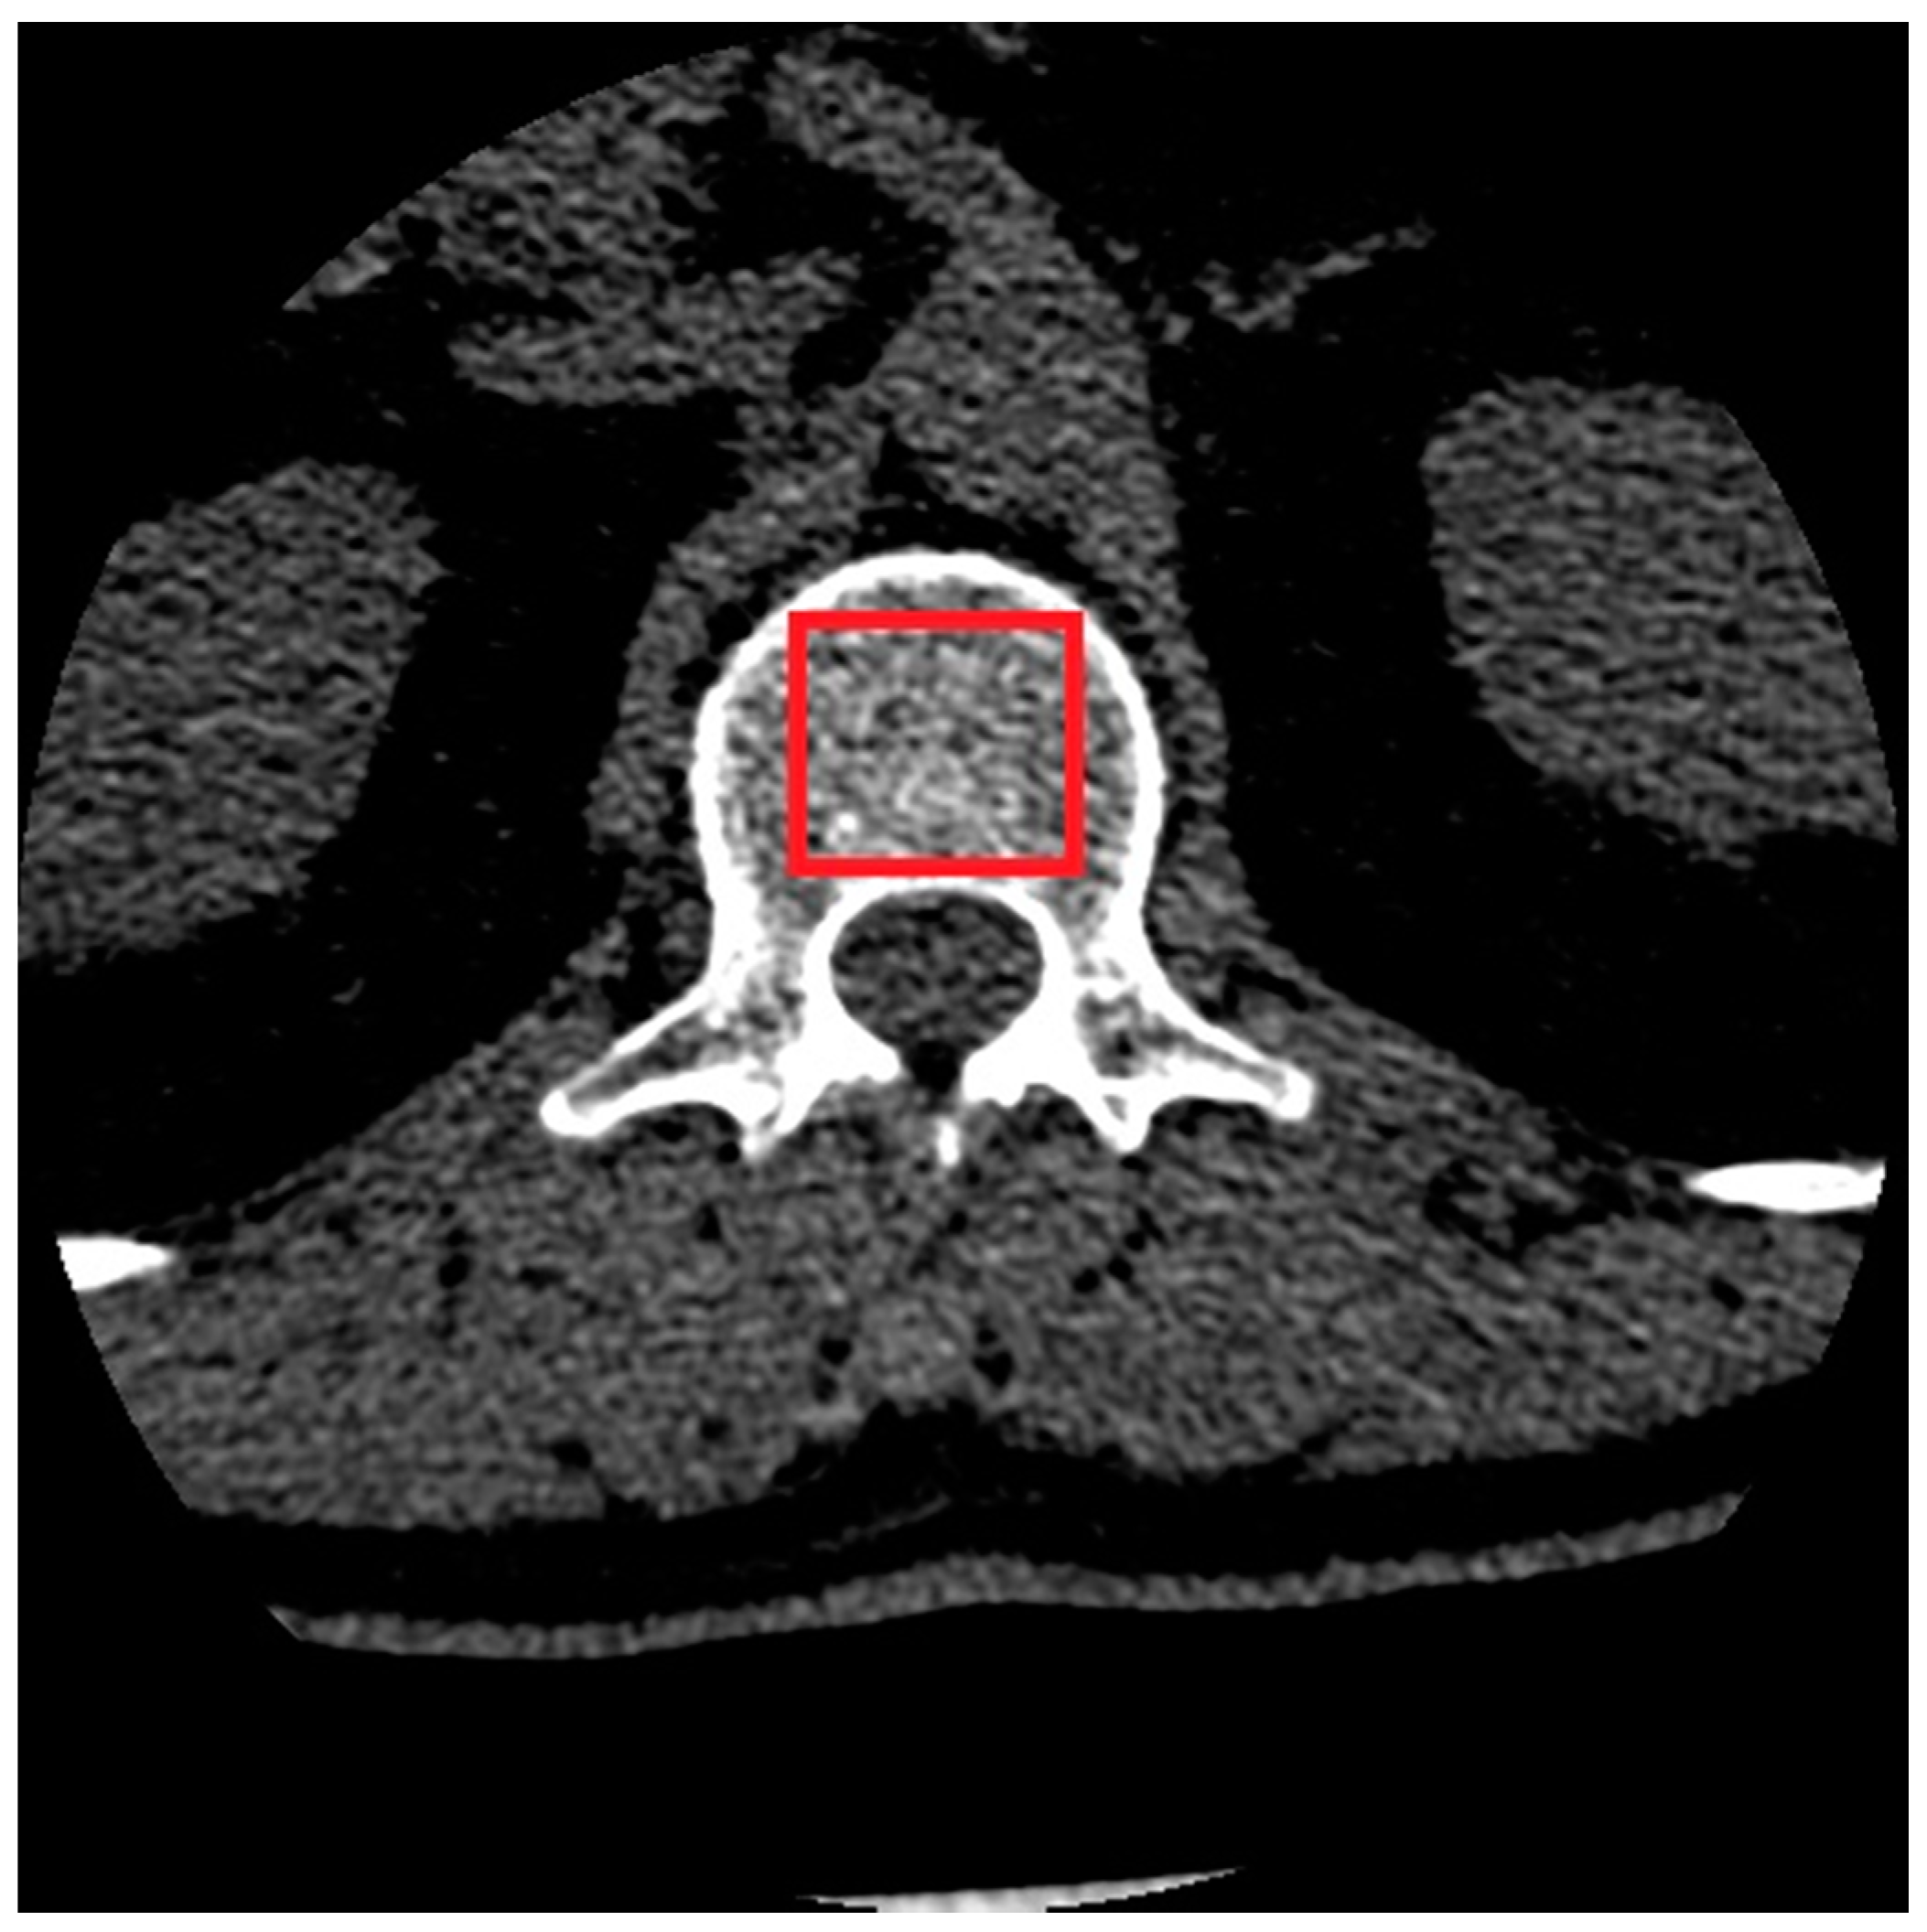

2.1. Material

2.2. Image Preprocessing